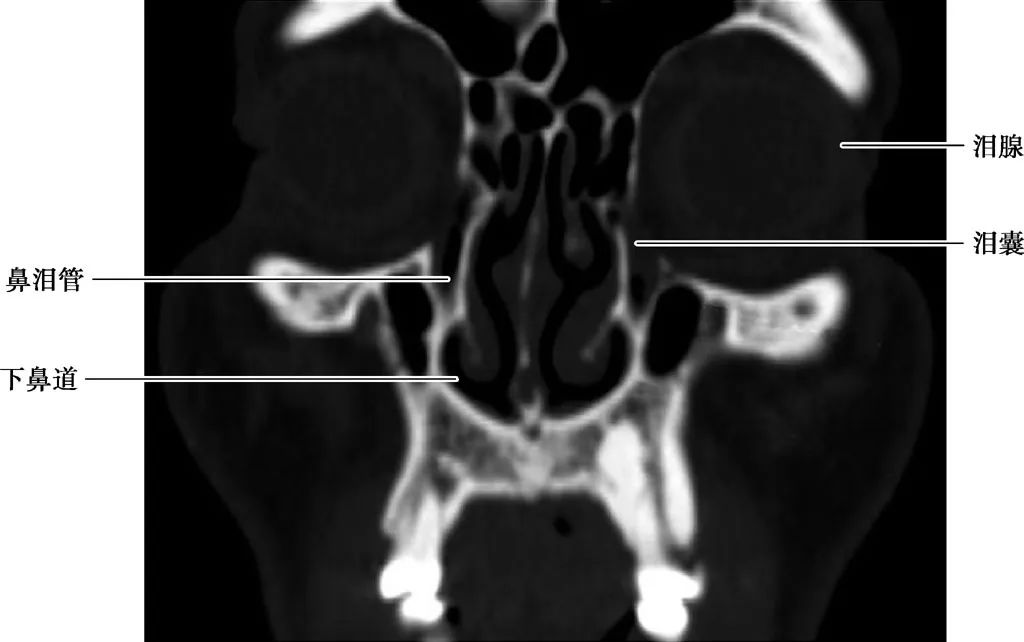

(CT冠状面)

A.岩尖层面;B.耳蜗层面;C.前庭窗层面;D.蜗窗层面;E.总骨脚层面;F.面神经管乳突段层面1.颈动脉管;2.鼓膜张肌;3.咽鼓管;4.颞颌关节;5.耳蜗;6.面神经管迷路段;7.面神经管鼓室段;8.锤骨头;9.盾板;10.锤骨颈;11.锤骨柄;12.鼓膜张肌;13.内耳道;14.前庭;15.上骨半规管;16.外骨半规管;17.前庭窗;18.乳突窦入口;19.圆窗;20.耳蜗导水管;21.总骨脚;22.弓形下窝;23.颈静脉球;24.乙状窦;25.后骨半规管;26.面神经管乳突段